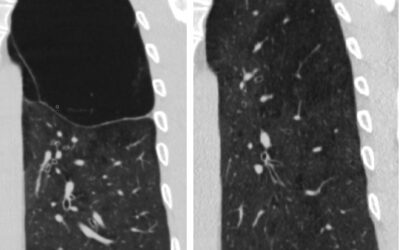

ფილტვის მოცულობის ბრონქოსკოპიული შემცირება ბულოზური ემფიზემის შემთხვევაშიპაციენტი 42 წ მამაკაცი. აქტიური მწეველი. თავს ავად გრძნობს რამოდენიმე თვეა. ჩივილები: ძლიერი ქოშინი ფიზიკურ დატვირთვაზე, ჰაერის უკმარისობა, საერთო სისუსტე. გულმკერდის კტ კვლევით - ორივე ფილტვის...